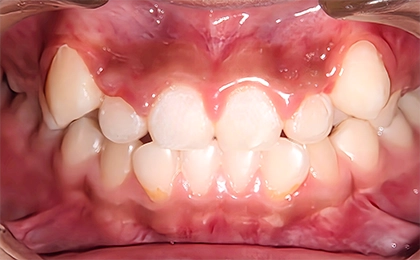

Case1 前歯のガタガタ、部分的な受け口

Before

治療内容 | 上のあごに固定式の拡大装置を装着し、あごを拡げてできた隙間で上の前歯のガタガタを治療し、永久歯列に生え変わるまで経過観察を行いました。 |

治療のリスク | 歯の生え変わりにより拡大装置が合わなくなることがあります。 |